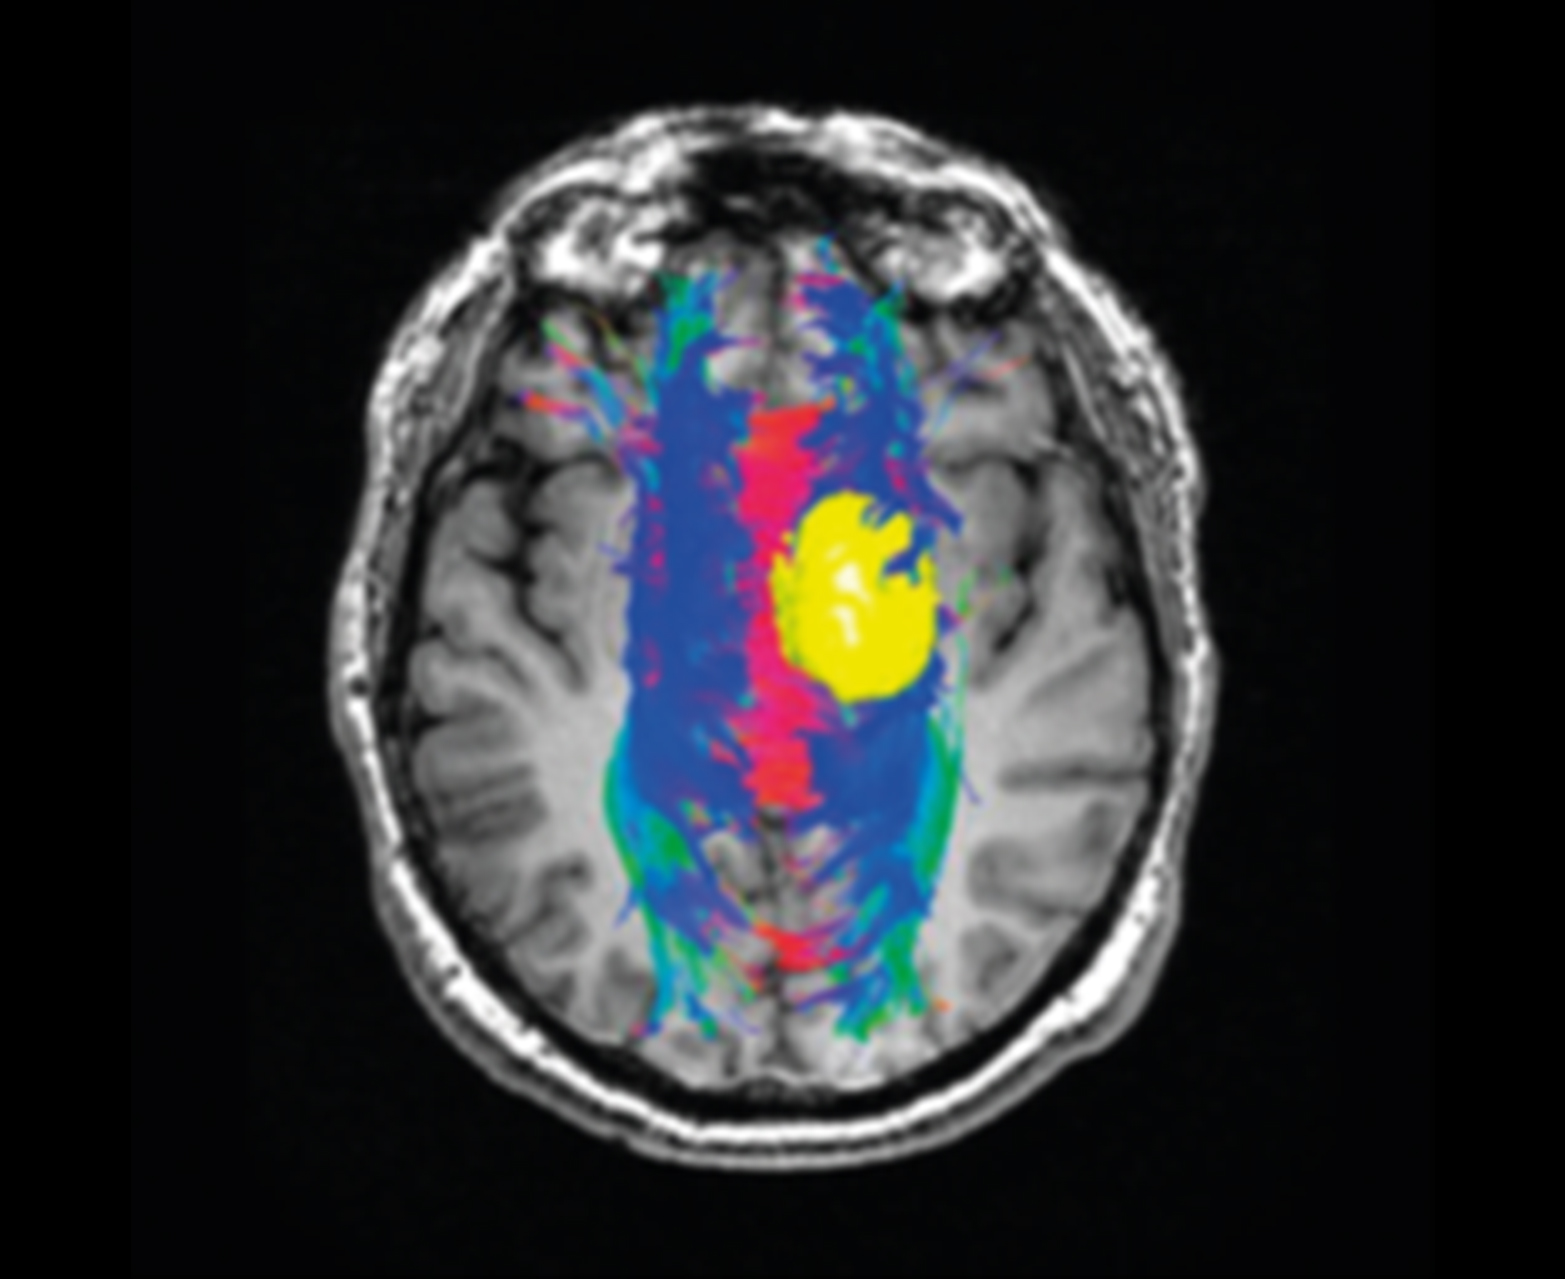

- Предоперационное планирование с трактографией и отображением волокон на обычных картах

Отслеживание волокна и объединение с обычными картами